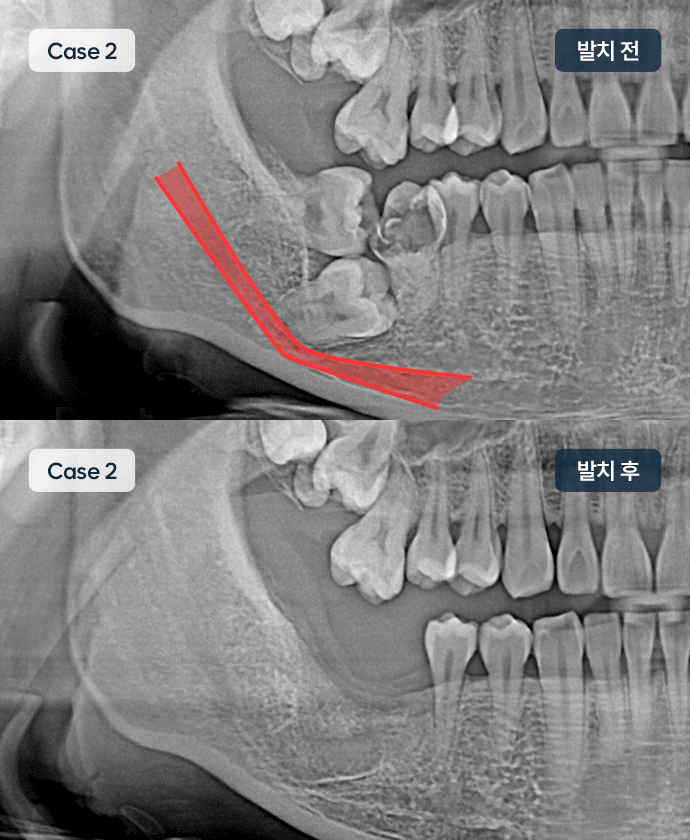

사랑니 발치

사랑니는 치아 가장 깊숙이 자리잡고 있어 양치가 안되는 경우가 많습니다.

이 경우 충치가 옆 어금니까지 번져, 어금니 발치 후 임플란트를 하는 경우도 종종 있어 관리가 필요합니다.

특히 매복인 경우, 신경에 가깝게 자리할 때가 있어 수술시 주의가 필요합니다.

대학병원 추천 케이스

매복 사랑니· 치아 발치